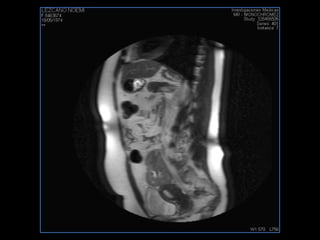

LIC ALEJANDRA GALVEZ RM DE ABDOMEN

PROTOCOLO abdomen COR T2, AXIAL supresion grasa AX T1 +SAG T2  CON   GADOLINIO :  COR T1+AX T1(DIN) SAT: NO  FASE: RL THK: 6MM  COIL:  GAP: (FACTOR 1.4) 2MM FOV: 40 CM NEX:2 SINCRONIZACION RESPIRATORIA EN 3 O 4 CICLOS ALE

resonancia de abdomen